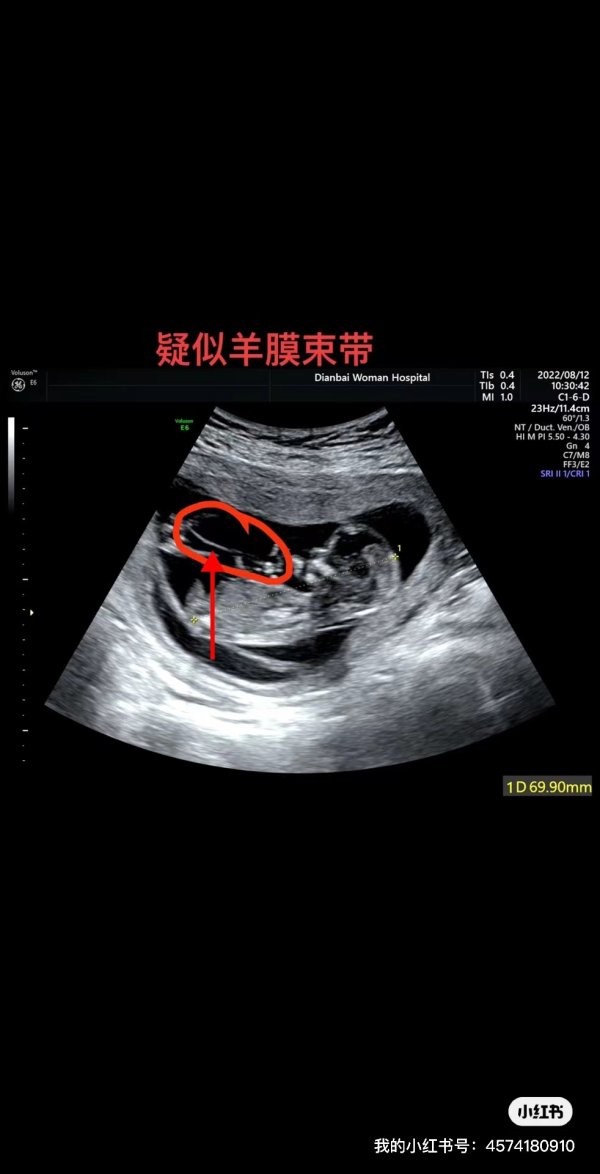

根据现在医院提供给我们的超声检查存图,早在NT第一次检查的时候就已经存在了异常,在存图里面都能看到有了羊膜束带,只是他们不承认而已,不承认又不敢书面给我保证说哪个不是羊膜束带,更气人的是根据胎儿超声检查指南,孕早期超声检查需要保留胎儿“双上肢、双下肢”的切面图,然而该院拷贝给我们的存图里没有发现有这几个部位的切面图,这充分的说明了,一,要么当时根本就没有认真去检查这几个部位,故没有相应的切面图。二,要不就是后面在我投诉后他们自查发现了存图有异常故毁灭证据,导致现在就没有这类存图给我们。超声科主任马全位还口口声声告诉我他们是看完存图后发现没有异常才出报告,然而事实证明他在放屁,10点26分出的报告,最后一张存图时间却为10点31分零9秒,按他说的看完存图出报告,报告时间不应该是在最后一张存图的后面吗?撒谎都不先打个草稿,真的,我奉劝大家以后产检一定要擦亮眼睛,我们就是一个惨痛的教训。几千块的产检换来的是一大堆不负责的医生来开展,换来的是一堆信口雌黄推卸责任的满口胡言,换来的是被他们当作草芥一样的收割!